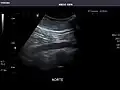

Aorta: Visualized portions normal in caliber, 16 x 15 mm.

Aorta -